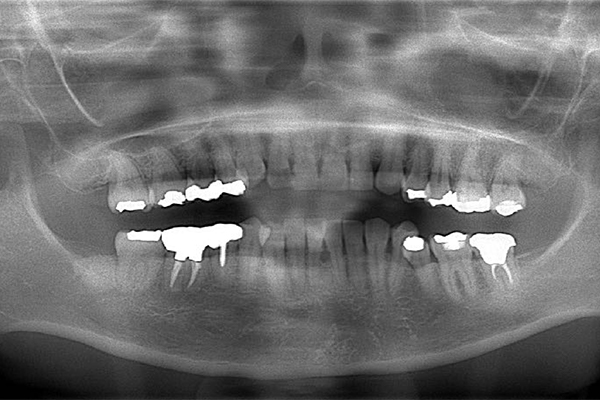

レントゲン写真(治療前)

【担当医師所見】

根の治療を3本すでに治療されています。1本根の奥の詰め物が疎になっていますので、根の部分の再治療も行う必要がありそうです。銀歯の中で虫歯になっているものもあります。